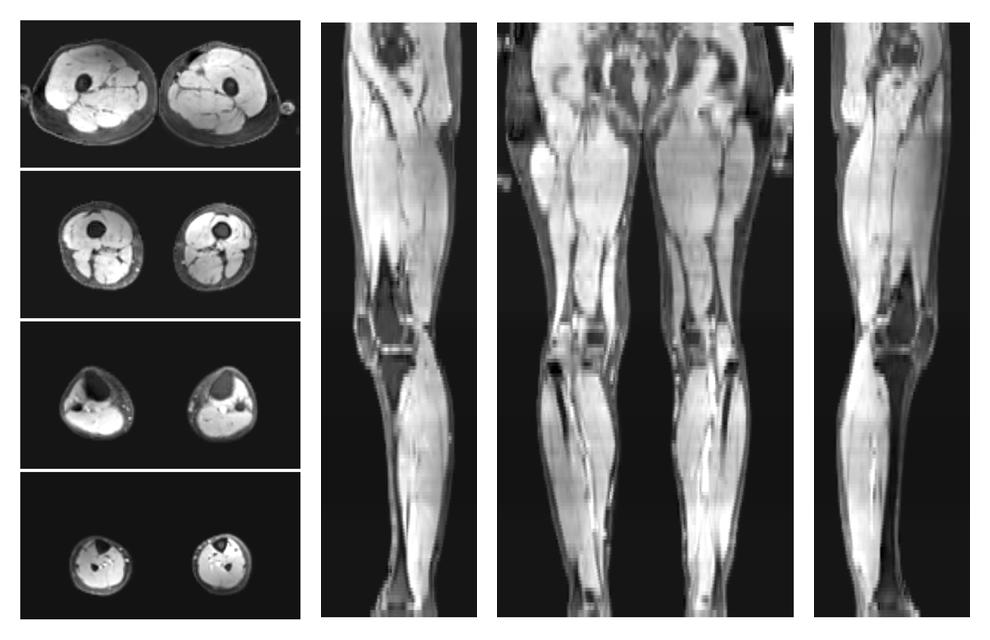

• Water only signal

The water part of the acquired multi-echo spin echo data.